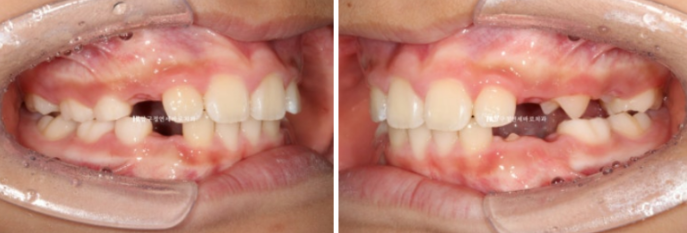

24.01

어금니 교합은 좋으며 그 사이 남아있던 유치가 대거 빠지고 영구치가 새로 나는 중입니다.

송곳니 날 자리를 충분히 마련해주었습니다.